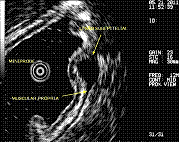

Por outro lado, a Ecoendoscopia permite também esclarecer se um determinado abaulamento da parede do tubo digestivo corresponde a uma compressão provocada por um órgão vizinho, ou a uma lesão da própria parede, camuflada, por uma mucosa de aspecto normal; neste caso, a Ecoendoscopia permite caracterizar essa lesão avaliando com precisão o seu tamanho, camada de origem na parede e diversas características morfológicas, podendo sugerir o diagnóstico mais provável. Em alguns doentes, poderão ser obtidas biópsias sob controlo ecográfico (punção-biópsia aspirativa com agulha fina) que complementam a investigação.

Relativamente à patologia biliar e pancreática, a USE pode ter aplicação na investigação de tumores do pâncreas ou das vias biliares, cálculos (litíase) da vesícula ou das vias biliares, estudo da pancreatite crónica, colecções líquidas do pâncreas, entre outras. Uma possível aplicação terapêutica da USE envolve justamente, em casos seleccionados, a drenagem de lesões císticas do pâncreas, drenagem da via biliar e até mesmo a realização de derivações bilio-digestivas.